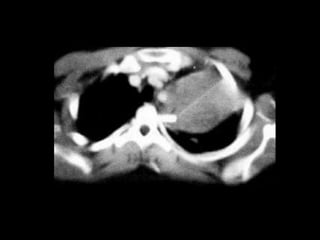

TOMOGRAFIA

v. braquiocef T a. subclavia v.subclavia v. axilar clavícula E a. subclavia carótidas primitivas

v. braquiocef. T E carótidas primitivas a.subclavia v. braquiocef. v. axilar clavícula